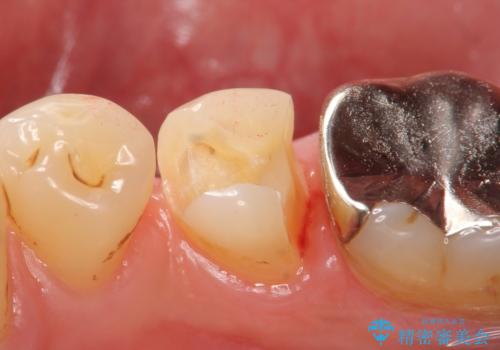

- 右下5番目の歯がしみるので診て欲しいといらっしゃった方の症例です。

古い銀歯及び虫歯を除去後、PGA(ゴールド)インレーによる修復を行いました。